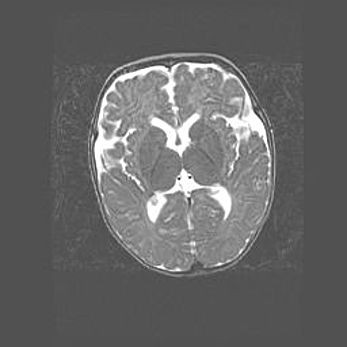

Сообщающаяся гидроцефалия. Кистозная энцефаломаляция головного мозга.

Возраст: 3 месяца 4 дня

Вес: 3100 г

Пол: женский

Окружность головы: 34 см

Срок гестации: 31 неделя

Кистозная энцефаломаляция головного мозга - одна из форм поражения головного мозга в детском возрасте. Характеризуется возникновением множественных и распространённых кист в коре, белом веществе и подкорковых образованиях головного мозга у плодов, новорождённых и детей раннего возраста. Развитие кистозной энцефаломаляции связано с внутриутробной асфиксией и гипотонией, родовой травмой, тромбозом синусов, пороками развития сосудов, инфекциями, сепсисом и другими причинами. Наиболее значимые инфекционные агенты: вирусы простого герпеса, цитомегалии, краснухи, токсоплазмы, энтеробактерии, золотистый стафилококк и другие.